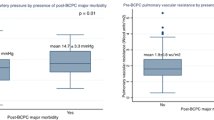

The median PI in those with intermediate- or late-Fontan-associated complications (n = 16, PI = 0.225) and those receiving (i) pulmonary vasodilator therapy (n = 7, PI = 0.1364), (ii) carvedilol (n = 7, PI = 0.20), or (iii) diuretics (n = 10, PI = 0.144) largely aligned with the overall population median (0.236), and included individuals from all three (low, medium, and high) PI subgroups (Fig. 3). While the absolute median PI values were lower in these patient subsets, the event rate was too small for statistical significance.

PI and adverse long-term outcomes. Distribution of Pulsatility Index (PI) in Patients with Fontan-associated complications, and those requiring pulmonary vasodilator or diuretic therapy at last follow-up. Median and interquartile range (IQR) are plotted. Abbreviations—FAD Fontan-associated disease or complications; PI pulsatility index